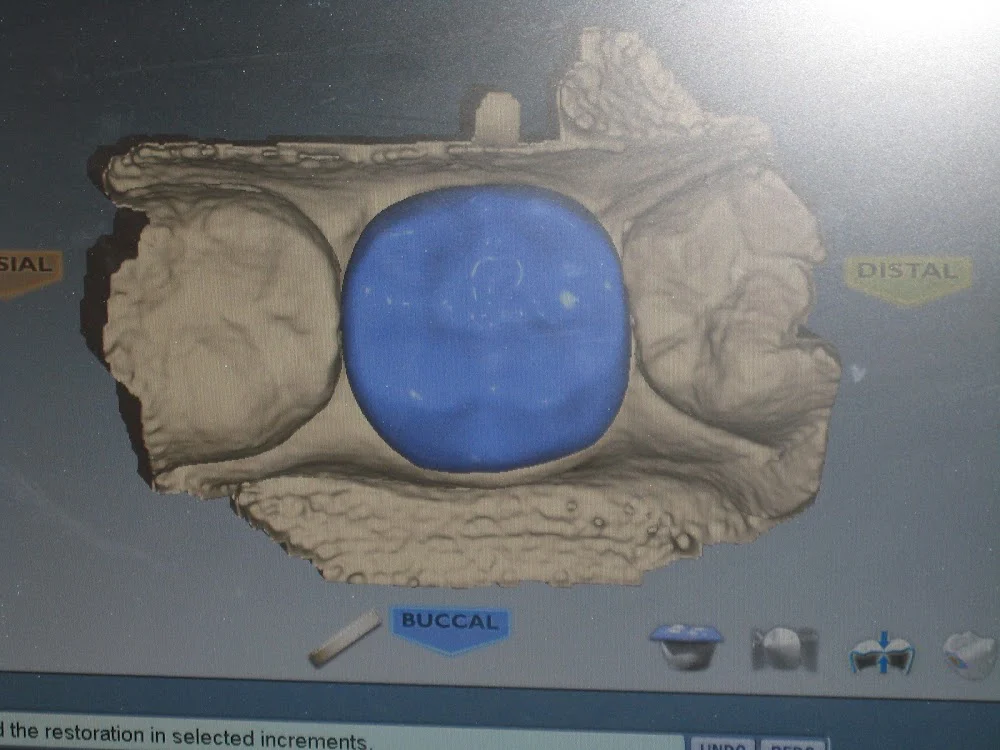

Comprehensive Dental Group Photos